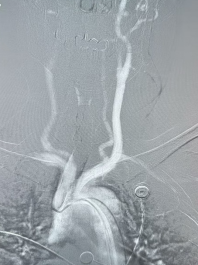

医生在控制室内“隔空”操作机器人控制台,完成复杂血管的造影检查

面对挑战,李永利教授团队决定启用高科技助手——脑血管介入手术机器人,联合脑血管介入手术辅助操作系统。手术开始后,医生在控制室内,通过操作台“隔空”指挥手术室内的机器人机械臂。在机器人稳定、灵活的操作下,团队成功完成了对复杂血管的超选(超选择性血管介入,是指利用特殊的导管和导丝,在医学影像设备的引导下,将导管插入到目标血管的更远端分支,以实现对特定血管区域的精准操作)。导管在数字路图引导下,如“听话的延长手”,依次精准进入所有目标血管,图像清晰,过程流畅。

李永利教授带领团队正在远程操控导丝导管到达指定血管及位置,大大减少患者及医生接受辐射的时间